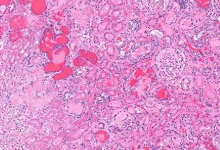

용혈요독 증후군은 대체로 장출혈성 대장균(O157:H7)이나 이질균, 살모넬라균 등에 오염된 음식 섭취로 발생합니다. 세균이 장벽에서 독소(Shiga toxin)를 생성해 혈관 내피를 손상시키며, 이로 인해 적혈구가 파괴되고 신장 내 모세혈관에 혈전이 형성됩니다. 비전형적 HUS는 유전적 결함, 면역억제제 사용, 폐렴구균 감염 등 다양한 원인에서 비롯될 수 있습니다. 특히 여름철 위생 관리 소홀 시 발생 위험이 높습니다. 안전한 조리와 식품 관리가 예방법의 핵심입니다.